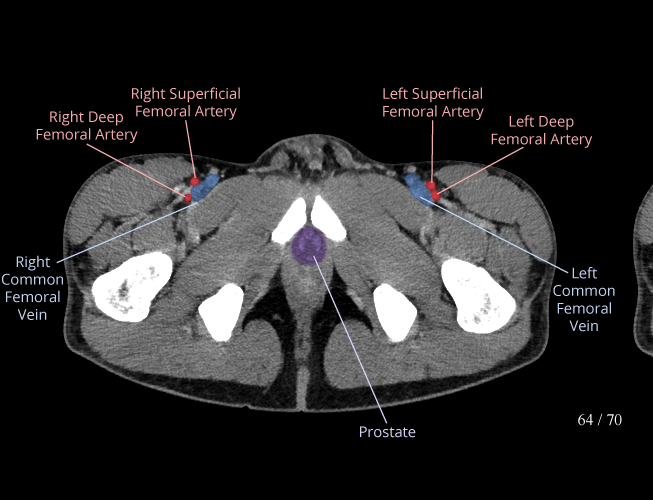

Pelvis

Covers pelvic MRI anatomy.